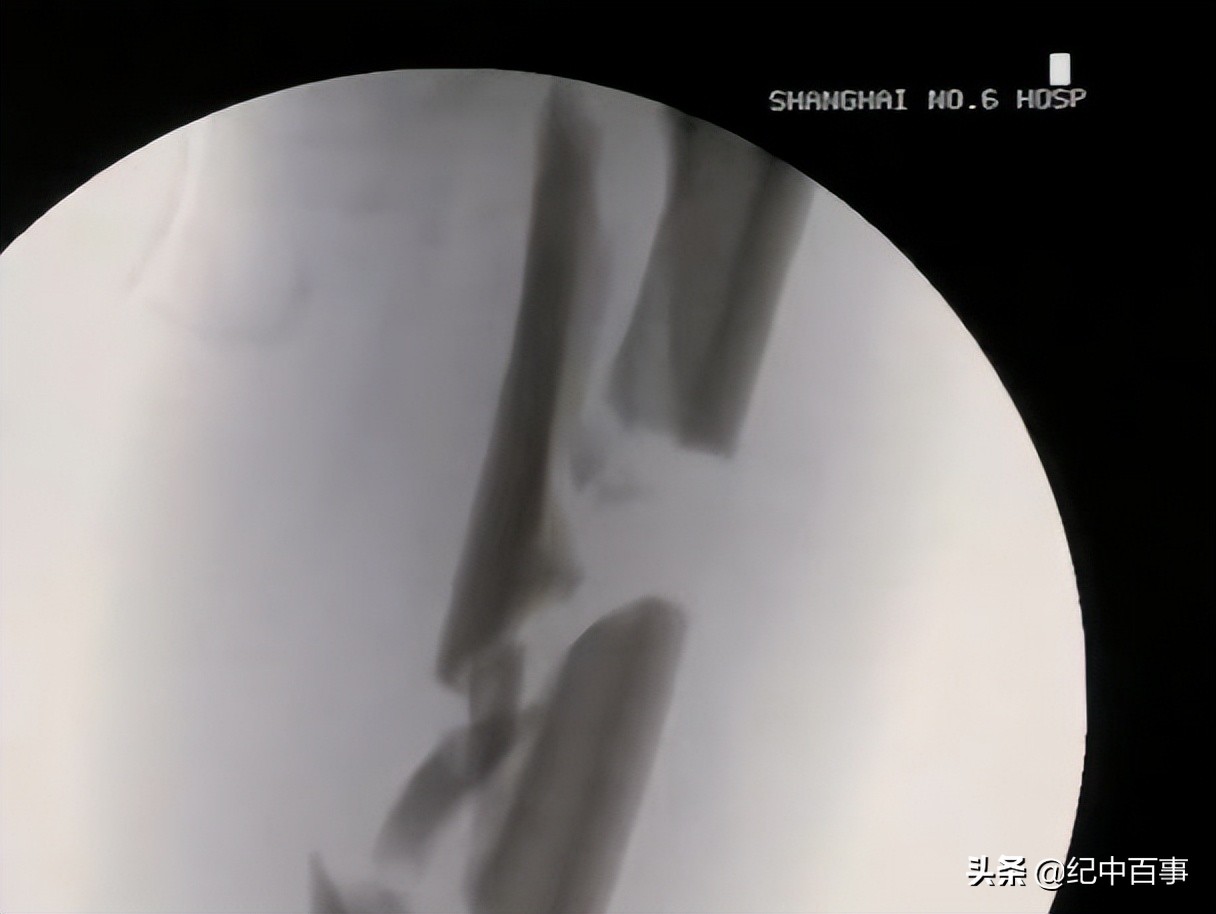

徐佩君仔细检查过戴双梅的身体状况后,开始检查断腿X光片,发现见断腿的小腿严重骨折,伤口占整条小腿的一半,伤口边缘血肉模糊。